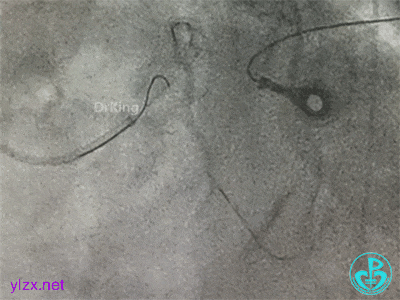

更换指引导管,导丝分别进入前降支和回旋支,球囊分别扩张前降支开口和回旋支开口,IVUS确认左主干及分支开口病变,前降支中段植入支架,对角支开口球囊扩张。

左主干分叉病变采取Crush双支架术式,回旋支开口植入支架,前降支开口球囊挤压后左主干到前降支植入支架(Crush双支架术式)。

导丝Rewire回旋支,非顺应性球囊分别后扩张前降支和回旋支支架,对吻扩张。